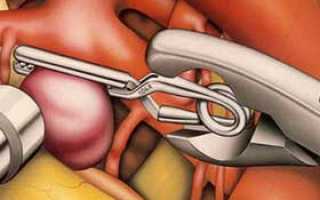

Когда речь заходит о клипировании аневризмы, подразумевается процедура, направленная на изоляцию аневризмы от общего кровообращения. Это достигается путем установки специальной клипсы на шейку пораженного сосуда.

В зависимости от типа аневризмы может понадобиться применение зажимов с обеих сторон. Для доступа к необходимой области выполняется трепанация черепа.

- Аневризма отключается от общего кровотока с помощью клипсы.

Операция требует от хирурга высокой точности и внимательности. В процессе используются различные микрохирургические инструменты. Если врач замечает, что сосуды истончены, он может обернуть их хирургической марлей или фрагментами мышцы. Это поможет снизить риск разрыва при повышении давления.